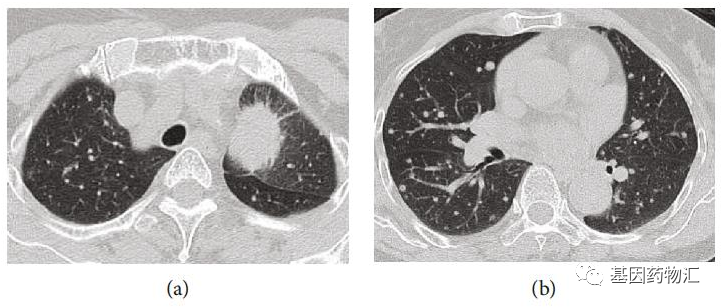

这名患者是一位74岁的老太太,毕生从未吸烟,在一次检查中发现血液癌胚抗原水平升高,因此接受了胸部CT检测,并最终确诊为T4N1M1c,即ⅣB期肺腺癌。

患者的胸部CT扫描图像,肺部巨大的阴影以及周围的小结节十分明显。